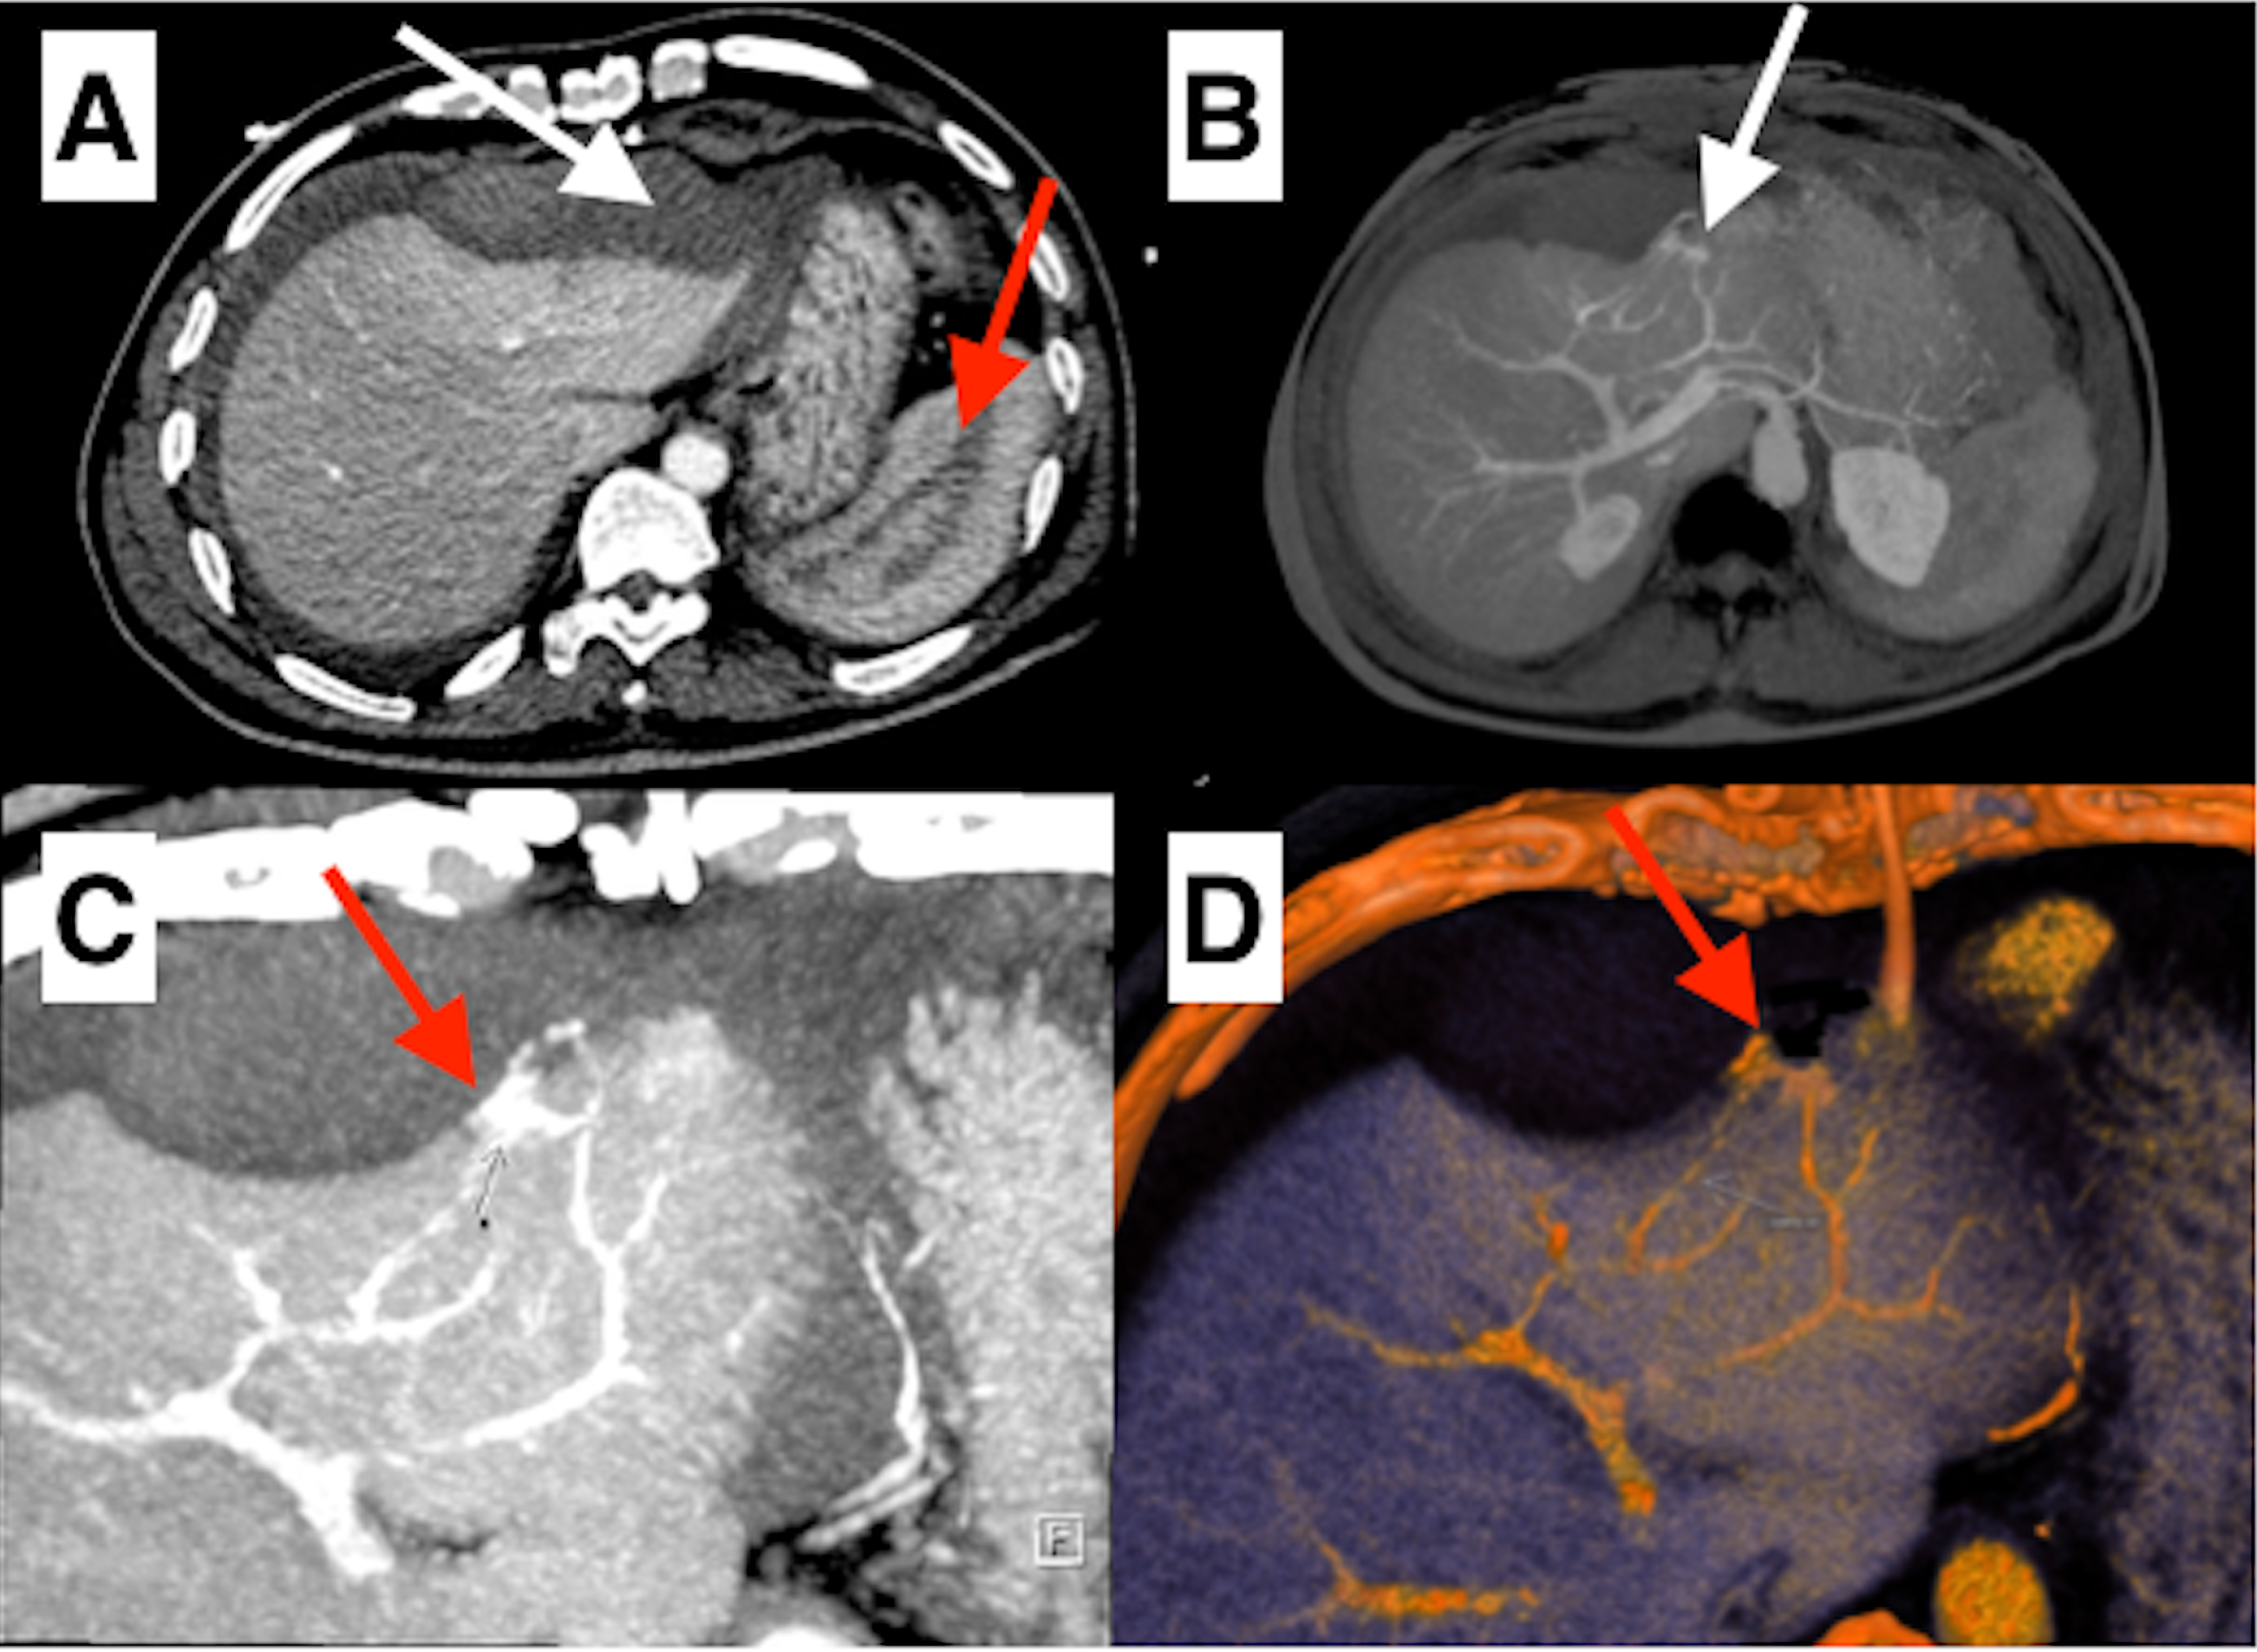

Since the patient’s haemoglobin decreased from 12.1 to 8.9 gm/dL, a computed tomography (CT) scan was done, which showed hemoperitoneum and hematoma in the perisplenic region and anterior to liver (Figure, A) with active contrast leak from a branch of left hepatic artery (Figure, B-D). He was managed conservatively with packed red blood transfusion in view of hemodynamic stability. The haemoglobin improved to 12.3 gm/dL and a repeat CT scan 48 hours later showed no active contrast extravasation or increase in the collection. The pigtail was removed after TTE and showed no accumulation of pericardial fluid. The further course was complicated by development of contrast-induced nephropathy, which resolved in a week. The patient was discharged and continues to do well at 1-month follow-up.